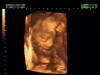

3D Sonogram Pictures